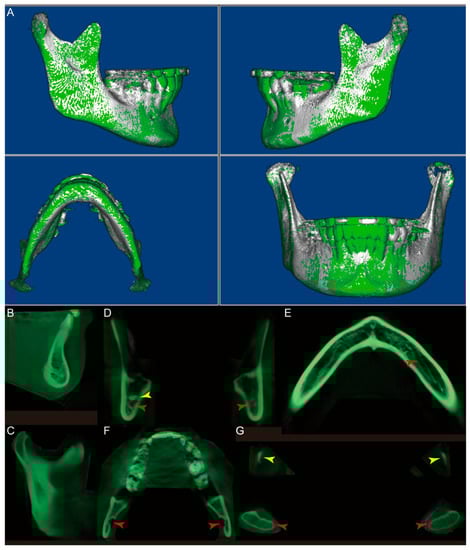

- Orient the CBCT to the right oblique view (Figure 1E), enlarge the CBCT, and change the “Seg Volumes” to identify the lower and upper density values in the appropriate range to differentiate the condyle from the surrounding structures (Figure 1F). This adjustment will produce a translucent view of the right condyle (orange arrow), glenoid fossa (yellow arrow), and remaining maxillary structures (Figure 1G). Sculpt the glenoid fossa along the inferior border and remaining maxillary structures.

- Repeat step 4 for the left condyle with the CBCT oriented to the left oblique view.

- (7)